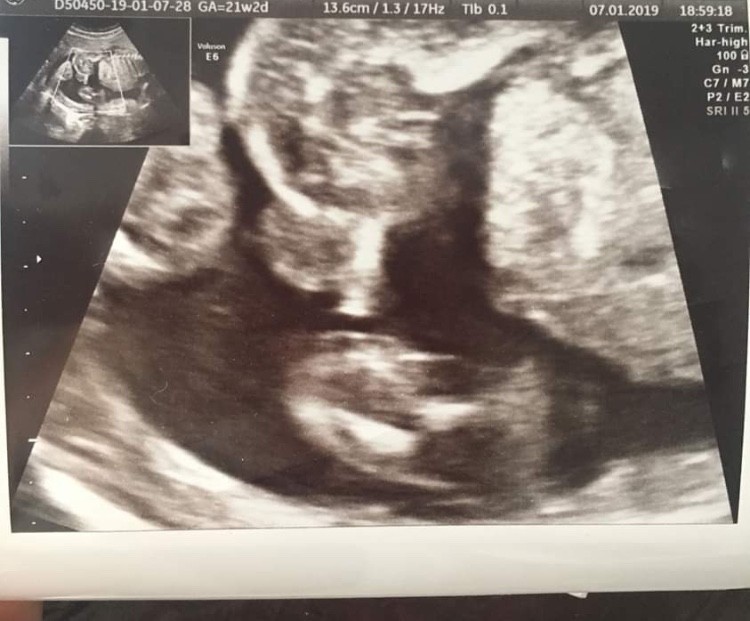

Witam w 19 tygodniu ciąży dowiedziałam się ze będę miała dziewczynkę w 20 tyg okazało się jednak , że to chłopak. Sama już nie wiem bo na jednym usg widać na pewno dziewuche a na drugim chłopca. Może to pempowina ?? Może ktoś mi pomoże rozwiązać ta zagadkę

• 4A8F5FF1-76CA-4DE0-AC12-5EDF08E820F2.jpg

4A8F5FF1-76CA-4DE0-AC12-5EDF08E820F2.jpg

596,4 KB · Wyświetleń: 43 708